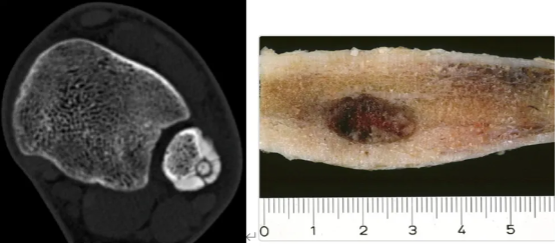

CT上显示为一个界限清晰的圆形或椭圆形软组织密度区。病变周围有反应性硬化,宏观上,骨样骨瘤是一个界限清晰的肿瘤,呈红色,质地柔软且易碎,直径为1.5-2厘米。(图片来源:WebPathology)